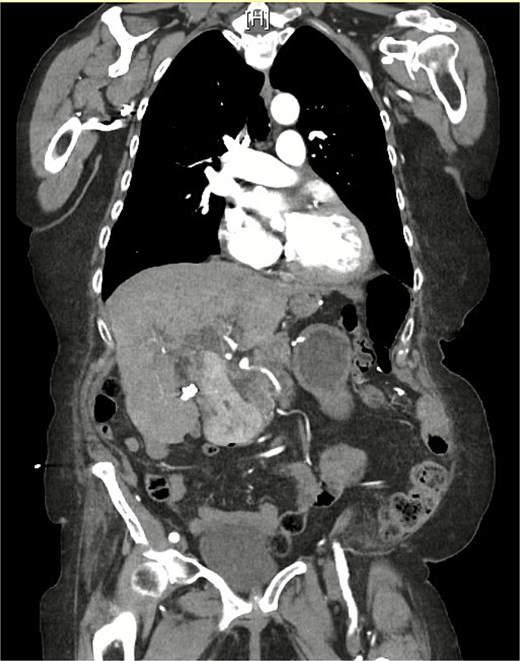

On examination, she was afebrile and hemodynamically stable. Her abdomen was mildly distended with epigastric tenderness and firmness. Laboratory workup revealed moderate leukocytosis (13.3 × 109/l), elevated lipase (288 U/l), and normal total bilirubin (0.8 mg/dl). Contrast-enhanced computed tomography (CT) demonstrated distention of the remnant stomach, duodenum (biliopancreatic limb), CBD, and intrahepatic ducts. A 9.0 × 3.4 cm heterogeneous mass was visualized in the duodenum, consistent with an obstructing gallstone (Figs 1–3).

CT demonstrating gallstone within the common bile duct 1 month prior to this admission.